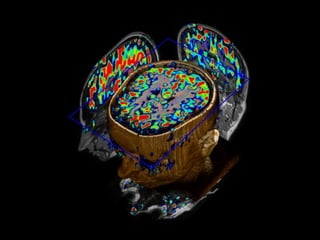

APARELHO DE RESONÂNCIA MAGNÉTICA

3 Teslas = 60.000 x campo magnético da Terra!

Imagem ponderada em T1

Imagem ponderada em T2

Contraste paramagnético

Alzheimer's disease   assymetric  atrophy of the right medial temporal  lobe